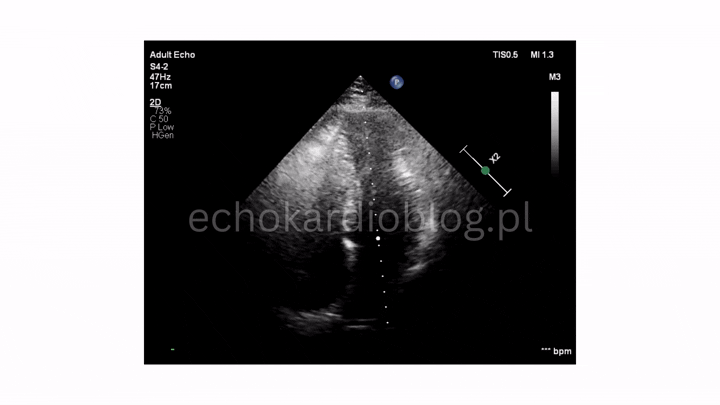

dwie długie i bardzo ruchome wegetacje na płatkach zastawki płucnej – pr podmostkowa w osi krótkiej